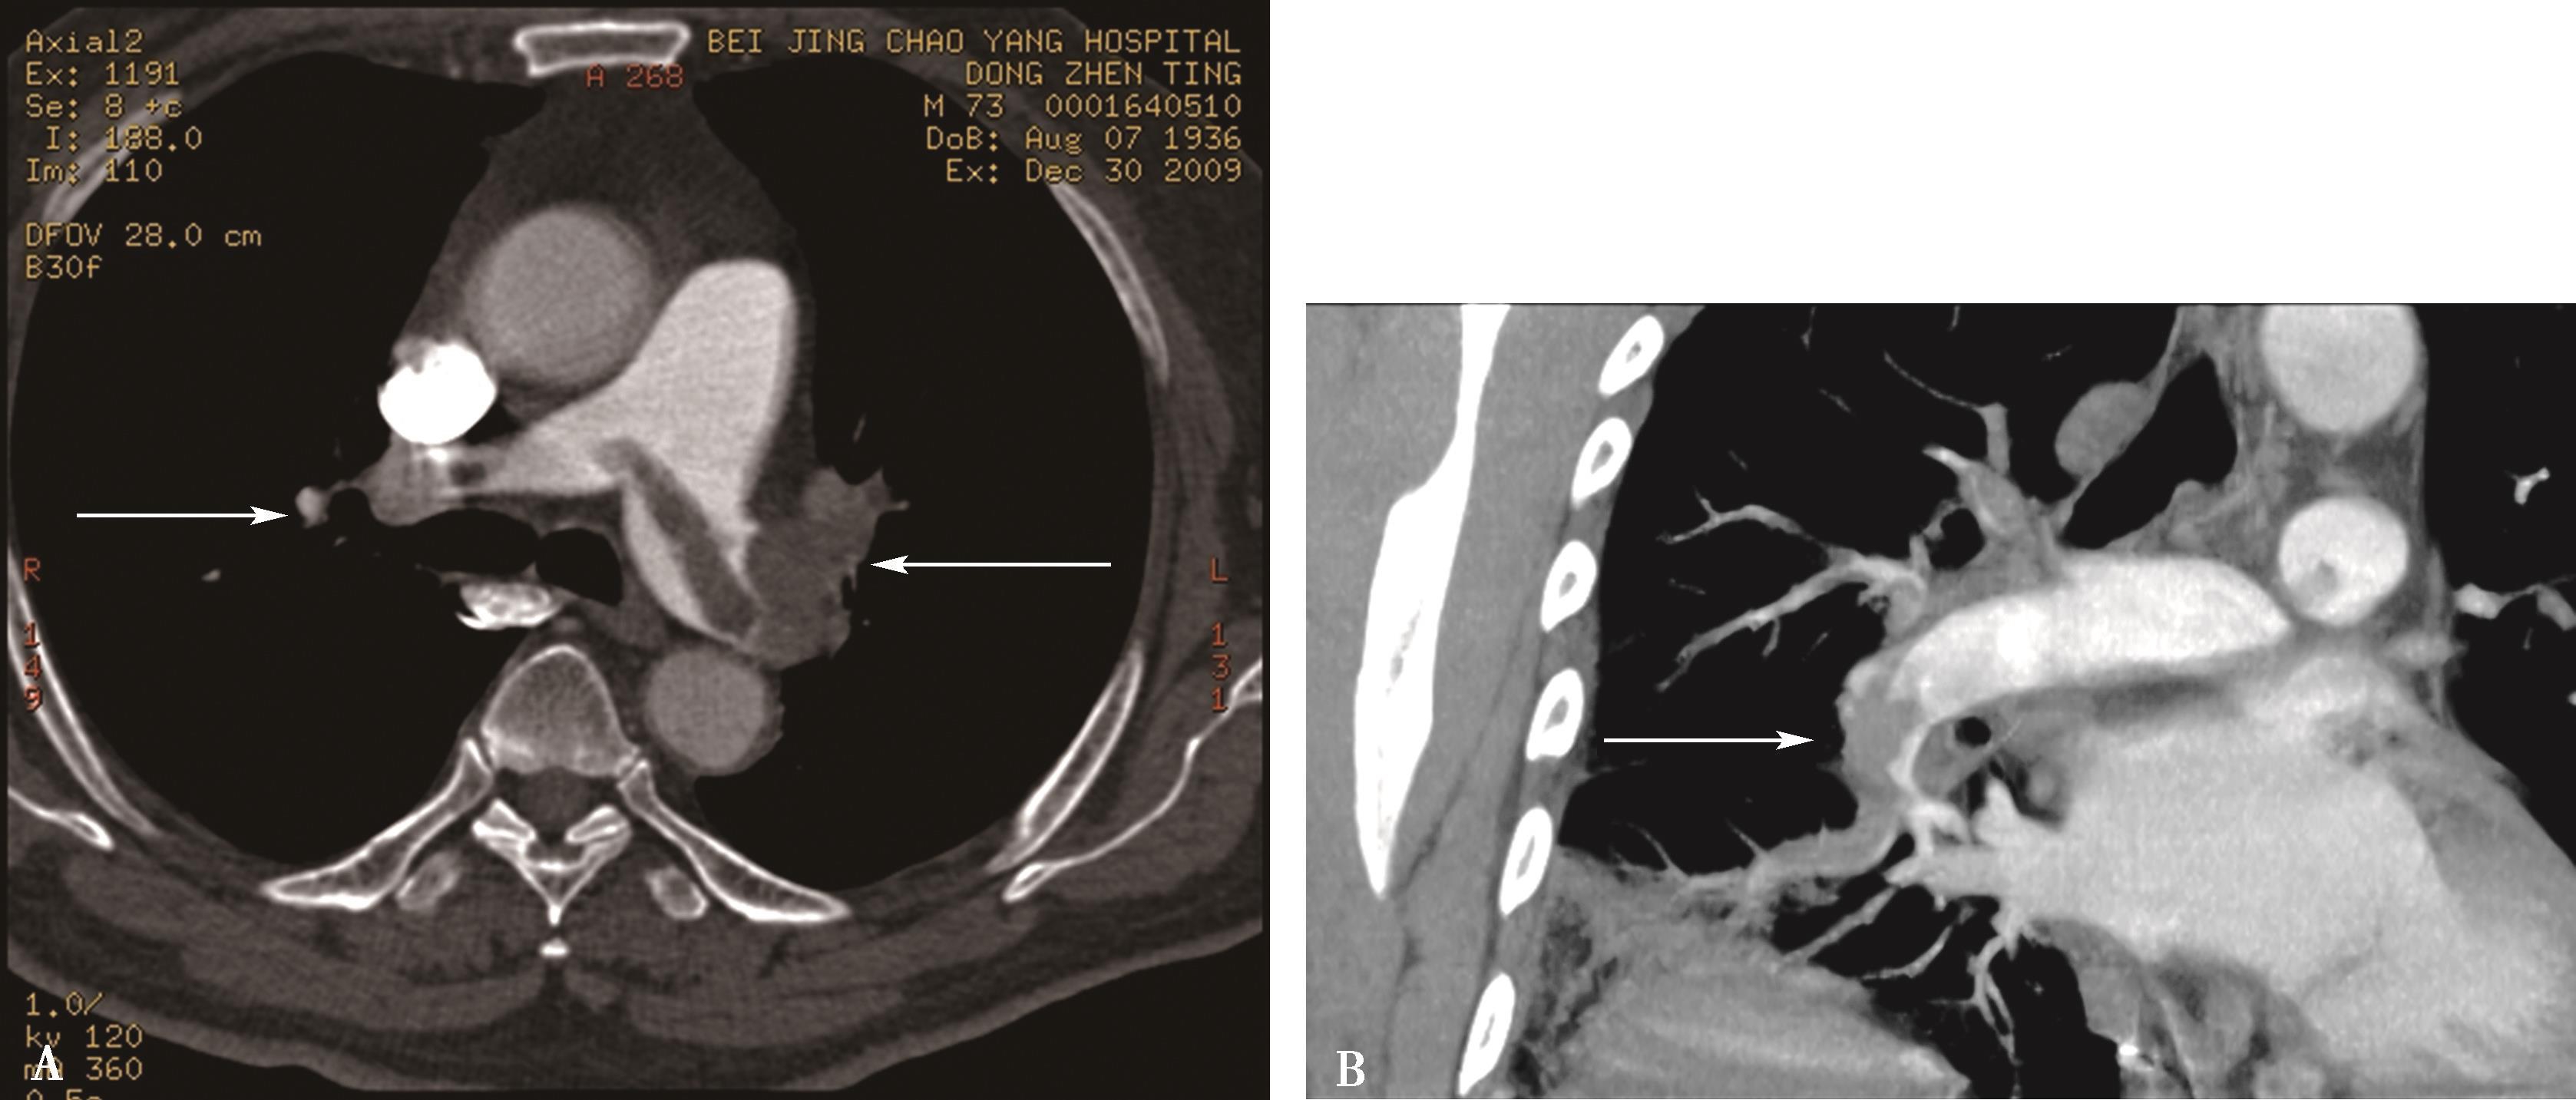

7.第二期延迟扫描可以弥补上述原因引起的肺静脉、左心房及左心房耳部充盈不满意,利于真伪影像的鉴别(图8-1-12)。

图8-1-12 左心房双期扫描女,62岁,阵发房颤,第一期扫描左心房耳部充盈缺损(A↑);第二期扫描左心房耳部充盈良好(B↑),为涡流所致,排除左房耳部血栓。